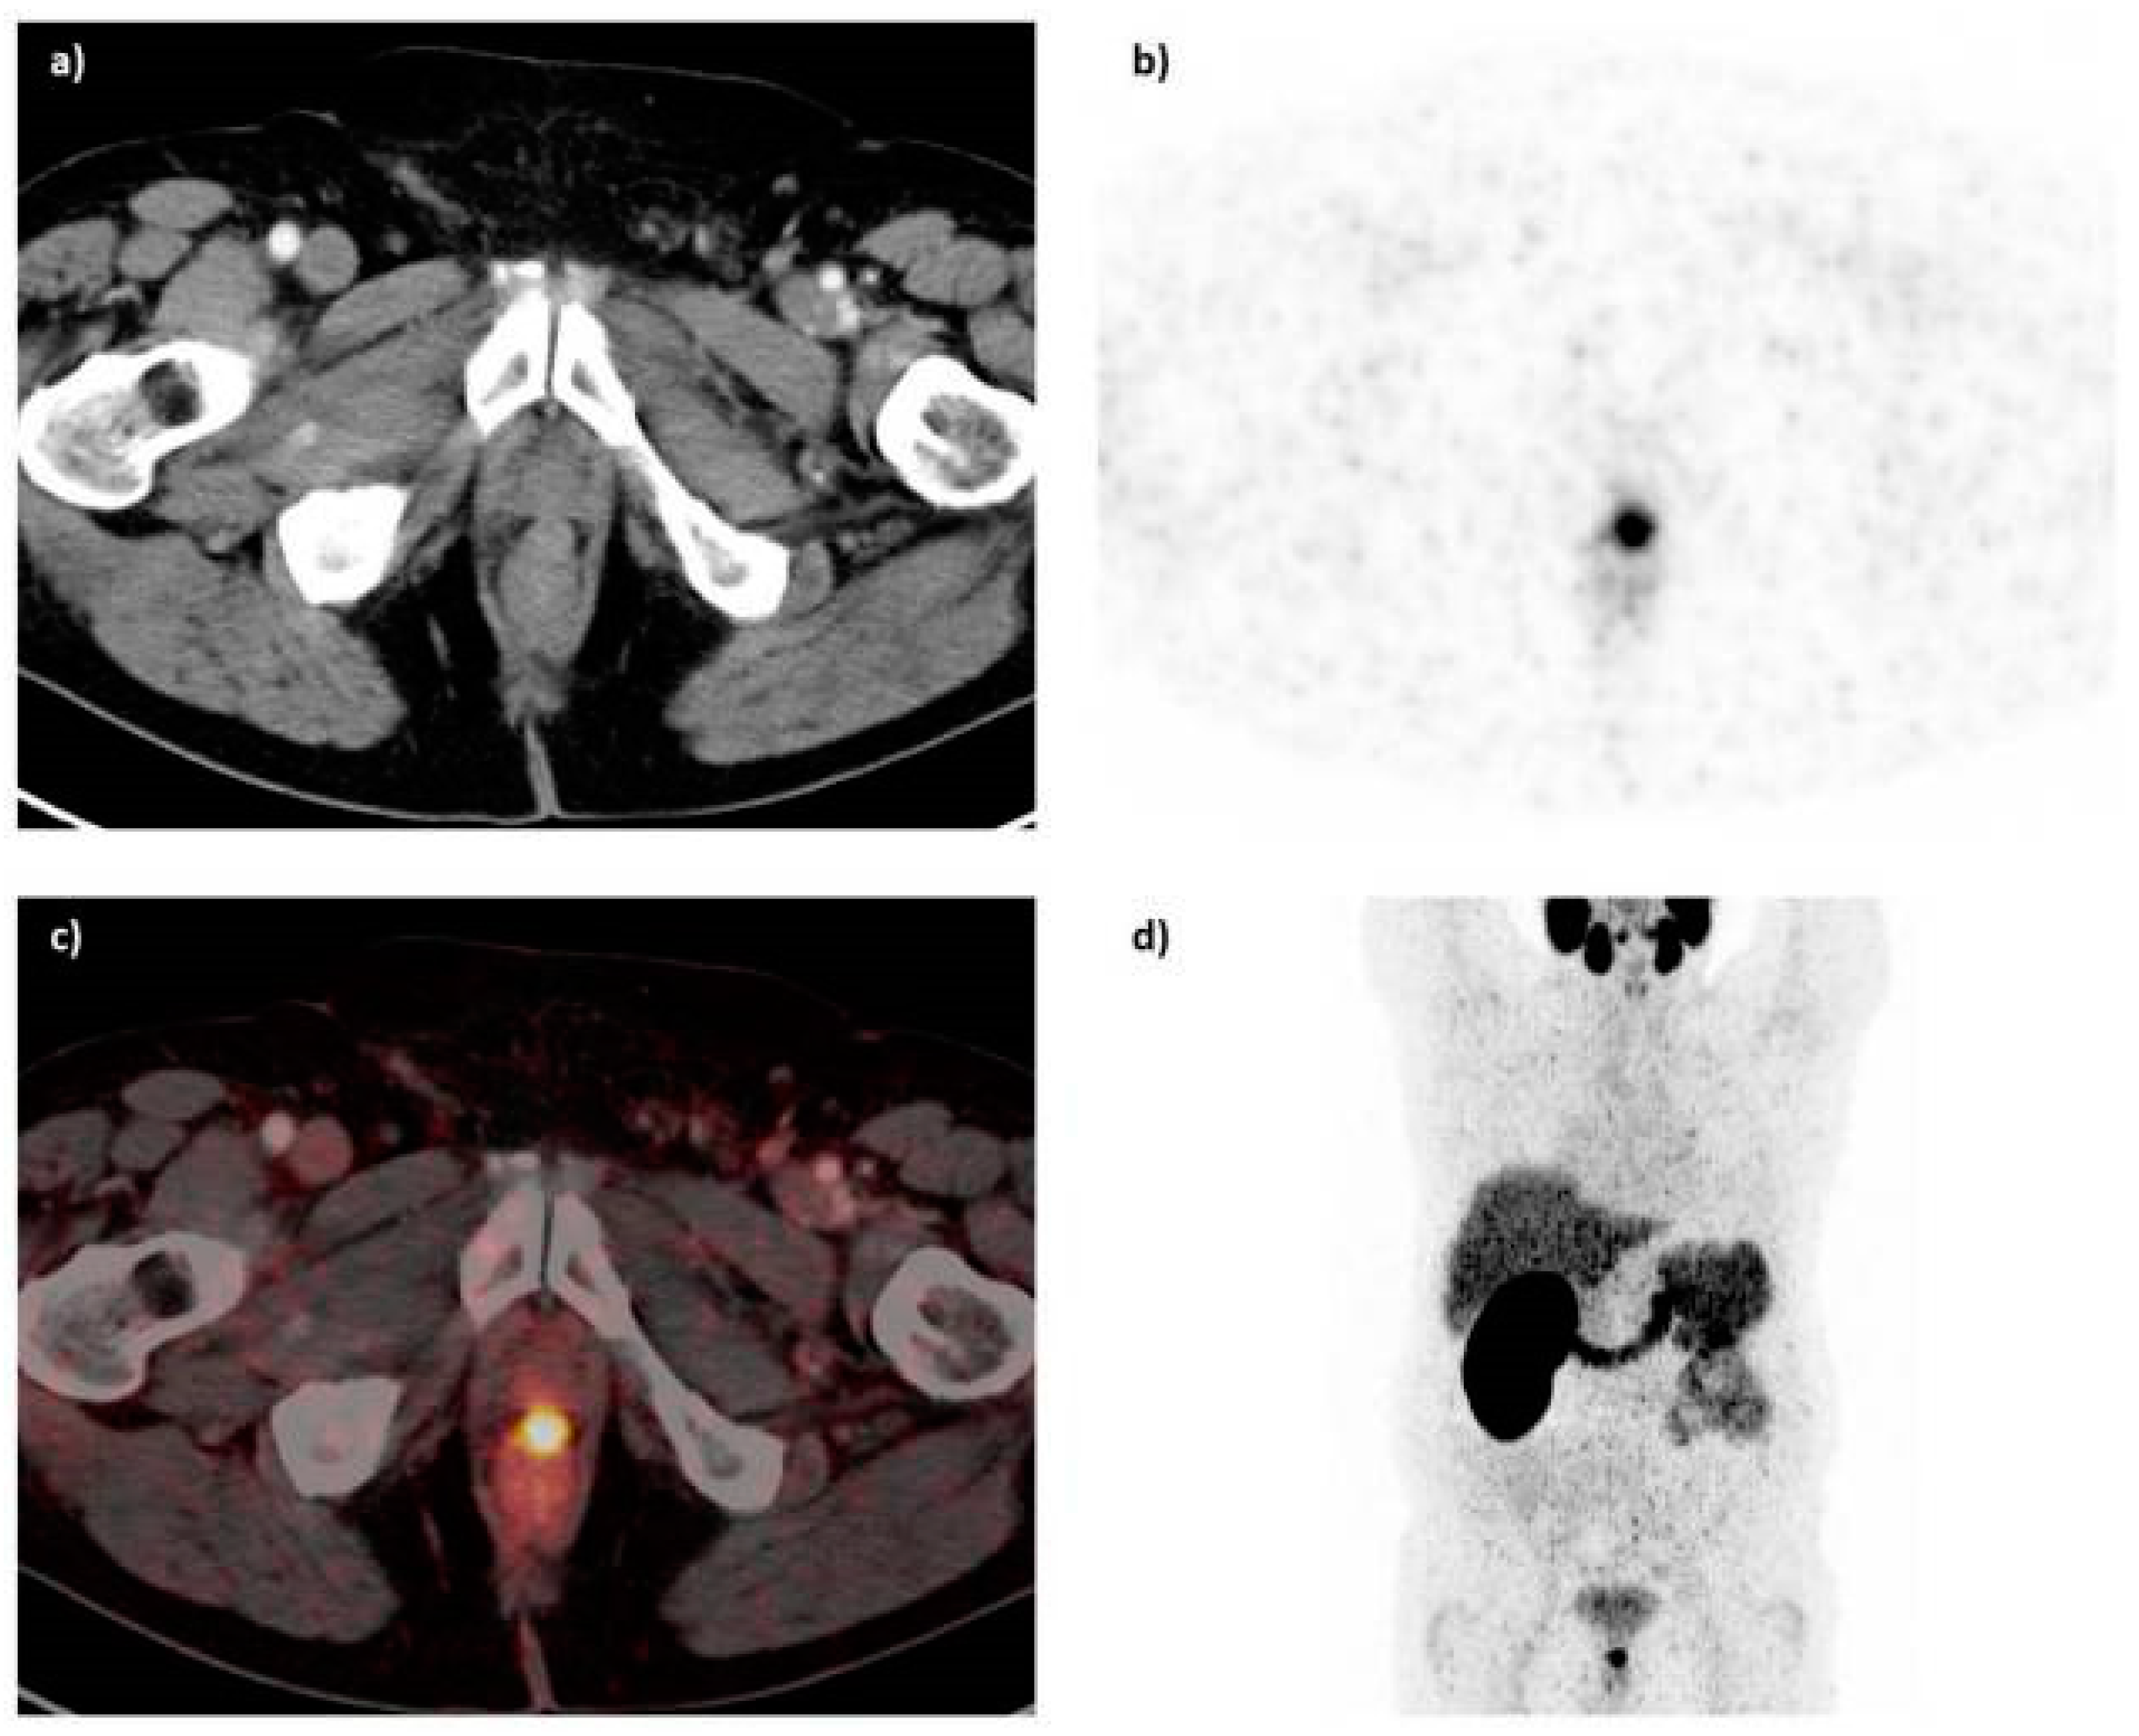

Figure 19.

68Ga-PSMA-11 PET/CT image of a patient with locally recurrent prostate cancer (PSA 3.7 ng/mL) after radical prostatectomy (SUVmax 12.4) who received 140 MBq of the 68Ga-labeled tracer molecule and was scanned at 1 h p.i.; (a) CT image; (b) PET image; (c) PET/CT fusion image; (d) MIP (Reprinted with permission of [145]).